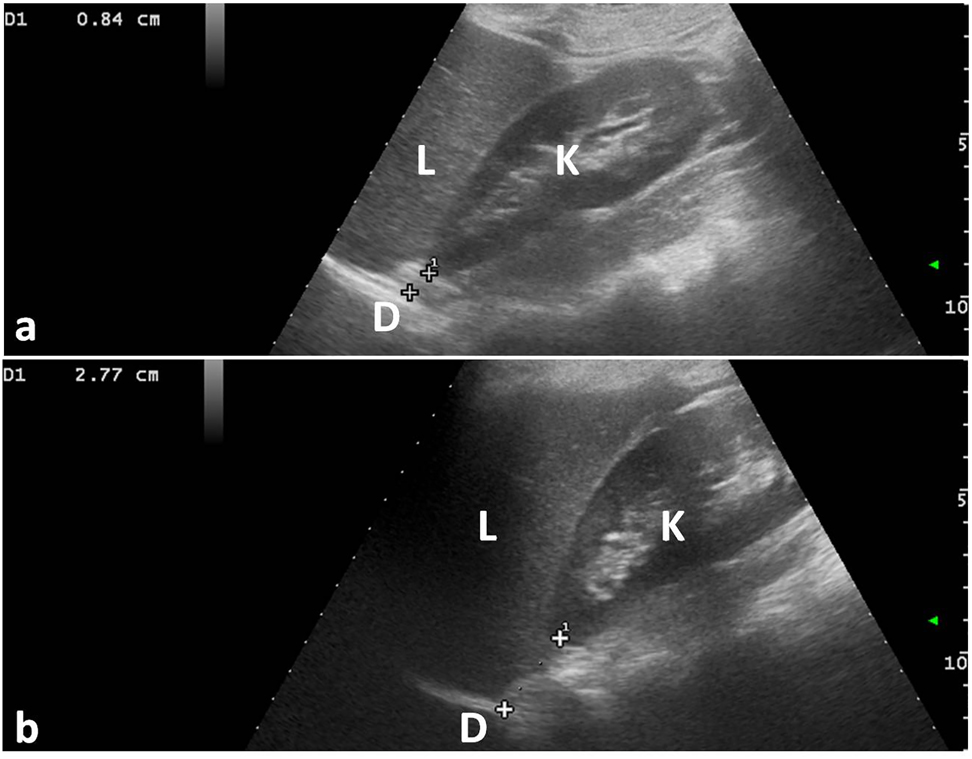

The distance between the kidney’s upper pole and the origin of the related diaphragmatic pillar was measured before and after treatment in maximum inspiration and maximum expiration for every patient (Figures 5 and 6).

Ultrasound measurement T0. The distance between the superior pole of the right kidney and the origin of the respective diaphragmatic pillar (calipers) was calculated during (a) maximal inspiration and (b) maximal expiration. K, right kidney; D, diaphragmatic pillar; L, liver.

Ultrasound measurement T1. The distance between the superior pole of the right kidney and the origin of the respective diaphragmatic pillar (calipers) was calculated during (a) maximal inspiration and (b) maximal expiration. K, right kidney; D, diaphragmatic pillar; L, liver.